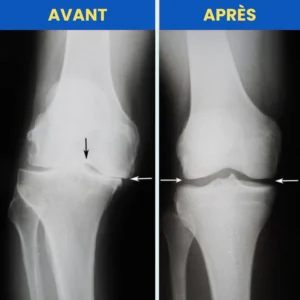

La douleur chronique au genou provient généralement d’un mauvais alignement de l’articulation et de l’usure du cartilage.

Avec l’âge, un mode de vie sédentaire ou des blessures, l’alignement naturel se dérègle, entraînant :

une mauvaise répartition du poids,

une usure accélérée du cartilage,

des douleurs de plus en plus intenses.

C’est ainsi que s’installent l’arthrose et la perte de mobilité.

L’OrthoRotule™ utilise la TAB pour réaligner votre rotule, réduire la pression sur le cartilage et soulager la douleur à la source.